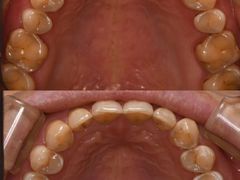

• -固瑞齿科(国贸门诊店)

小满爱逛吃 | 24-06-12

华华 | 24-06-12